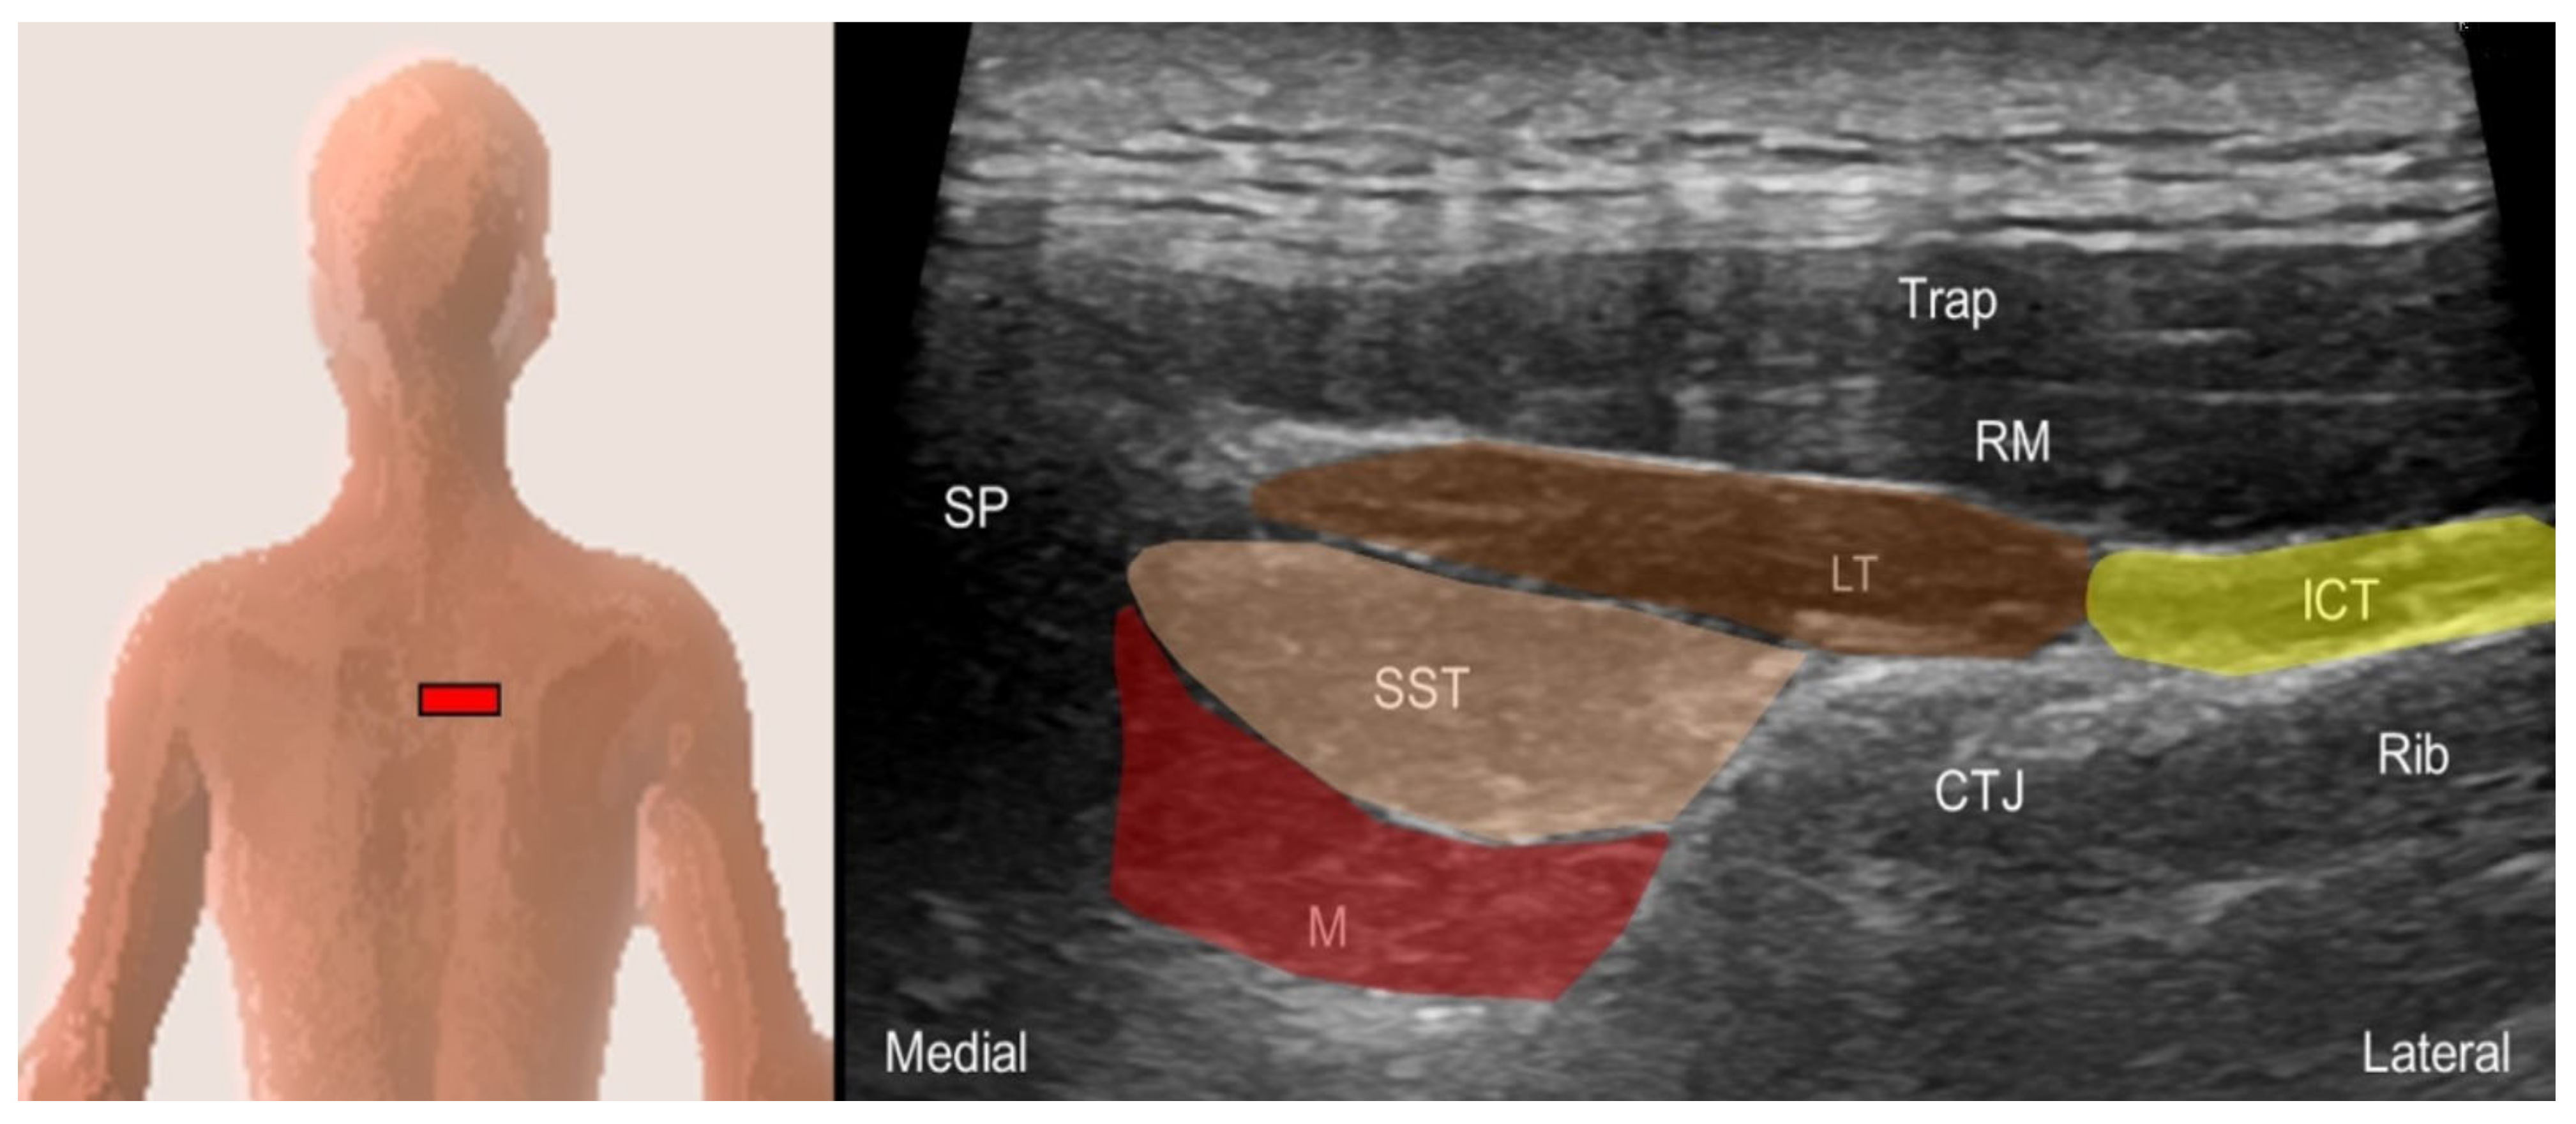

5.1.2. Sonographic Scanning

5.1.3. Clinical Relevance